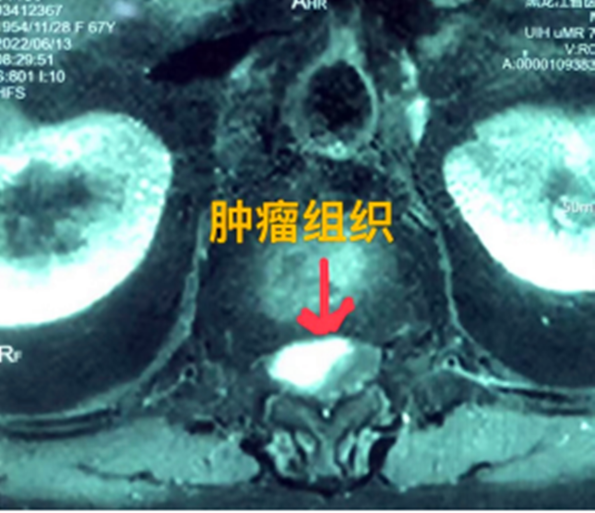

據(jù)省醫(yī)院神經(jīng)外一科陶宇醫(yī)生介紹,家住外地的張大娘最近總感覺雙下肢疼痛、無力,且排尿困難及便秘,伴有行走困難。時間長了,張大娘病情逐漸加重,劇烈的疼痛甚至讓她無法完整入睡。在當?shù)蒯t(yī)院,張大娘按腰椎肩盤突出接受治療,但未見好轉(zhuǎn),隨后進行的胸椎MRI(核磁共振)檢查,結(jié)果不禁讓張大娘和家屬瞠目結(jié)舌,原來張大娘患的竟然是少見的脊髓腫瘤。

張大娘住進了黑龍江省醫(yī)院神經(jīng)外一科,該科孫國章主任醫(yī)師熱情地接待了張大娘,并邀請骨外一科專家共同為她進行了聯(lián)合會診。發(fā)現(xiàn)張大娘病情十分復(fù)雜棘手,脊髓腫瘤體積較大,充滿髓腔且神經(jīng)已經(jīng)完全受壓,需要手術(shù)來完整切除。同時還發(fā)現(xiàn)張大娘的胸腰部曾受過兩次外傷,伴有多處骨折,這對接下來的手術(shù)操作帶來一定影響。